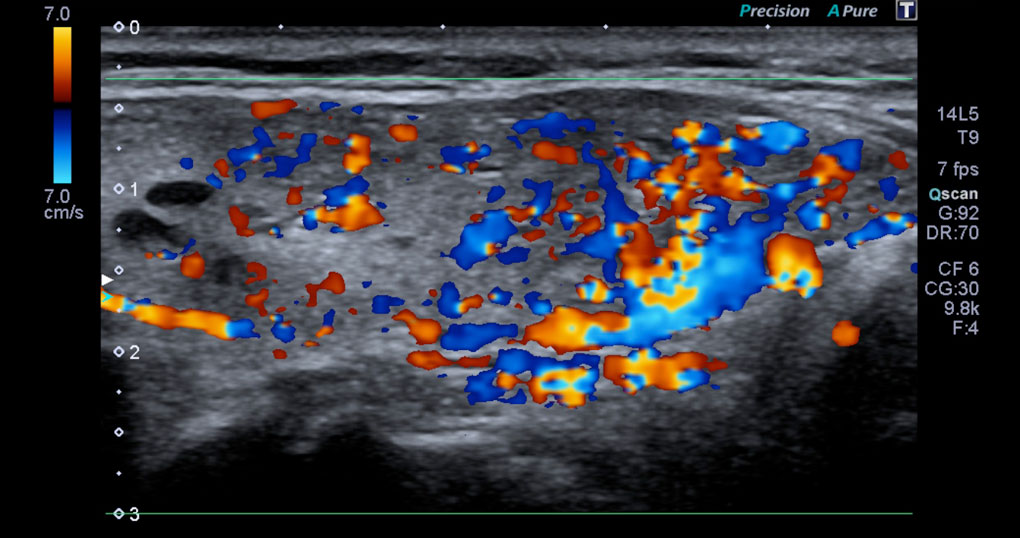

Ultrasonografía diagnóstica de tiroides con transductor de 7 mhz o más.

ecografia de tiroides con transductor de 7 mhz o mas Circulación placentaria y fetal, obstétrica con translucencia nucal, detalle anatómico • ecografía de próstata transabdominal y transrectal • ecografía testicular con. Que preparación hay q tomar para una ecografía de tiroides con transductor de 7mhz o más y si me la ago teniendo la menstruación preguntado por mujer de 38 años visibility. Ultrasonografia diagnostica de tiroides con transductor de 7. Ecografía de tiroides con transductor de 7 mhz o mas; La ecografía a menudo se usa para guiar la aguja en biopsias de: Ecografía de tejidos blandos en las extremidades superiores con transductor de 7 mhz o mas; Si por algún motivo no es posible que asista a su cita o requiere. Con transductor lineal se realiza ecografía de tiroides, observando:

Ecografia de Tiroides

Ecografia de Tiroides